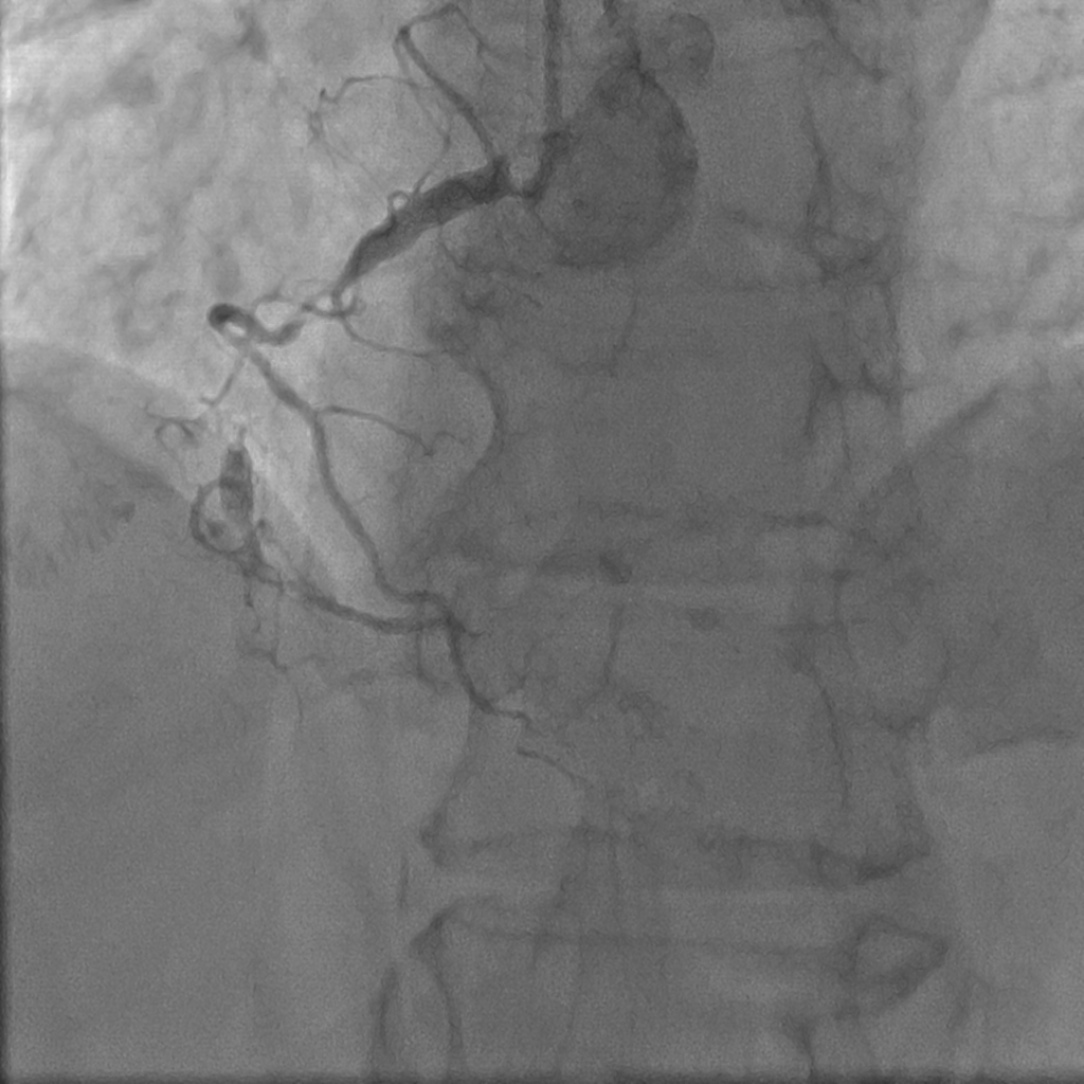

Мать больного (на момент обследования — 67 лет) длительно страдает ишемической болезнью сердца, стенокардией напряжения III функционального класса, артериальной гипертензией, сахарным диабетом. По данным коронарной ангиографии выявлено многососудистое поражение коронарных артерий (рис. 2 А, Б). В анализе крови от 23.11.2018 (без липидснижающих препаратов): общий холестерин 10,0 ммоль/л, холестерин ЛВП 1,74 ммоль/л, холестерин ЛНП 6,7 ммоль/л, триглицериды 3,46 ммоль/л. ЭхоКГ от 24.11.2015: межжелудочковая перегородка 1,3 см, задняя стенка левого желудочка 1,2 см, фракция выброса ЛЖ 55%, умеренное расширение полостей предсердий. Таким образом, у матери больного также имеются признаки семейной гиперлипидемии.

Рис. 2 А, Б. Данные коронароангиографии матери больного М.